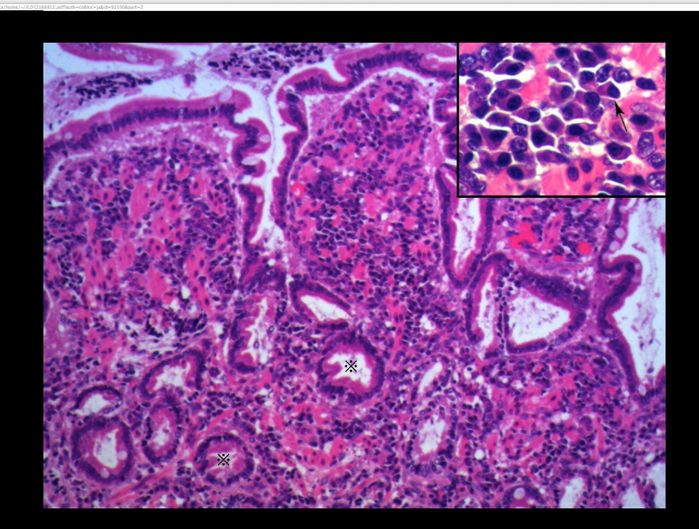

↑内視鏡で採取した腸の組織を顕微鏡で検査すると、炎症を起こしていることがわかります